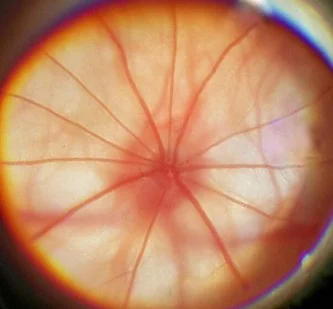

Офтальмоскопия и интегральная полуколичественная оценка состояния глазного дна